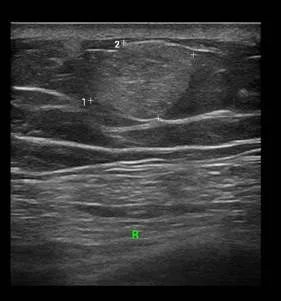

男性,38岁,来院行甲状腺B超检查,超声所见如图

解读:该男性甲状腺B超超声所见结节形态欠规则、纵横比失调,内回声不均,可见多发细点强回声,可见稀疏点状血流信号。恶性结节可能性大,需进一步检查。